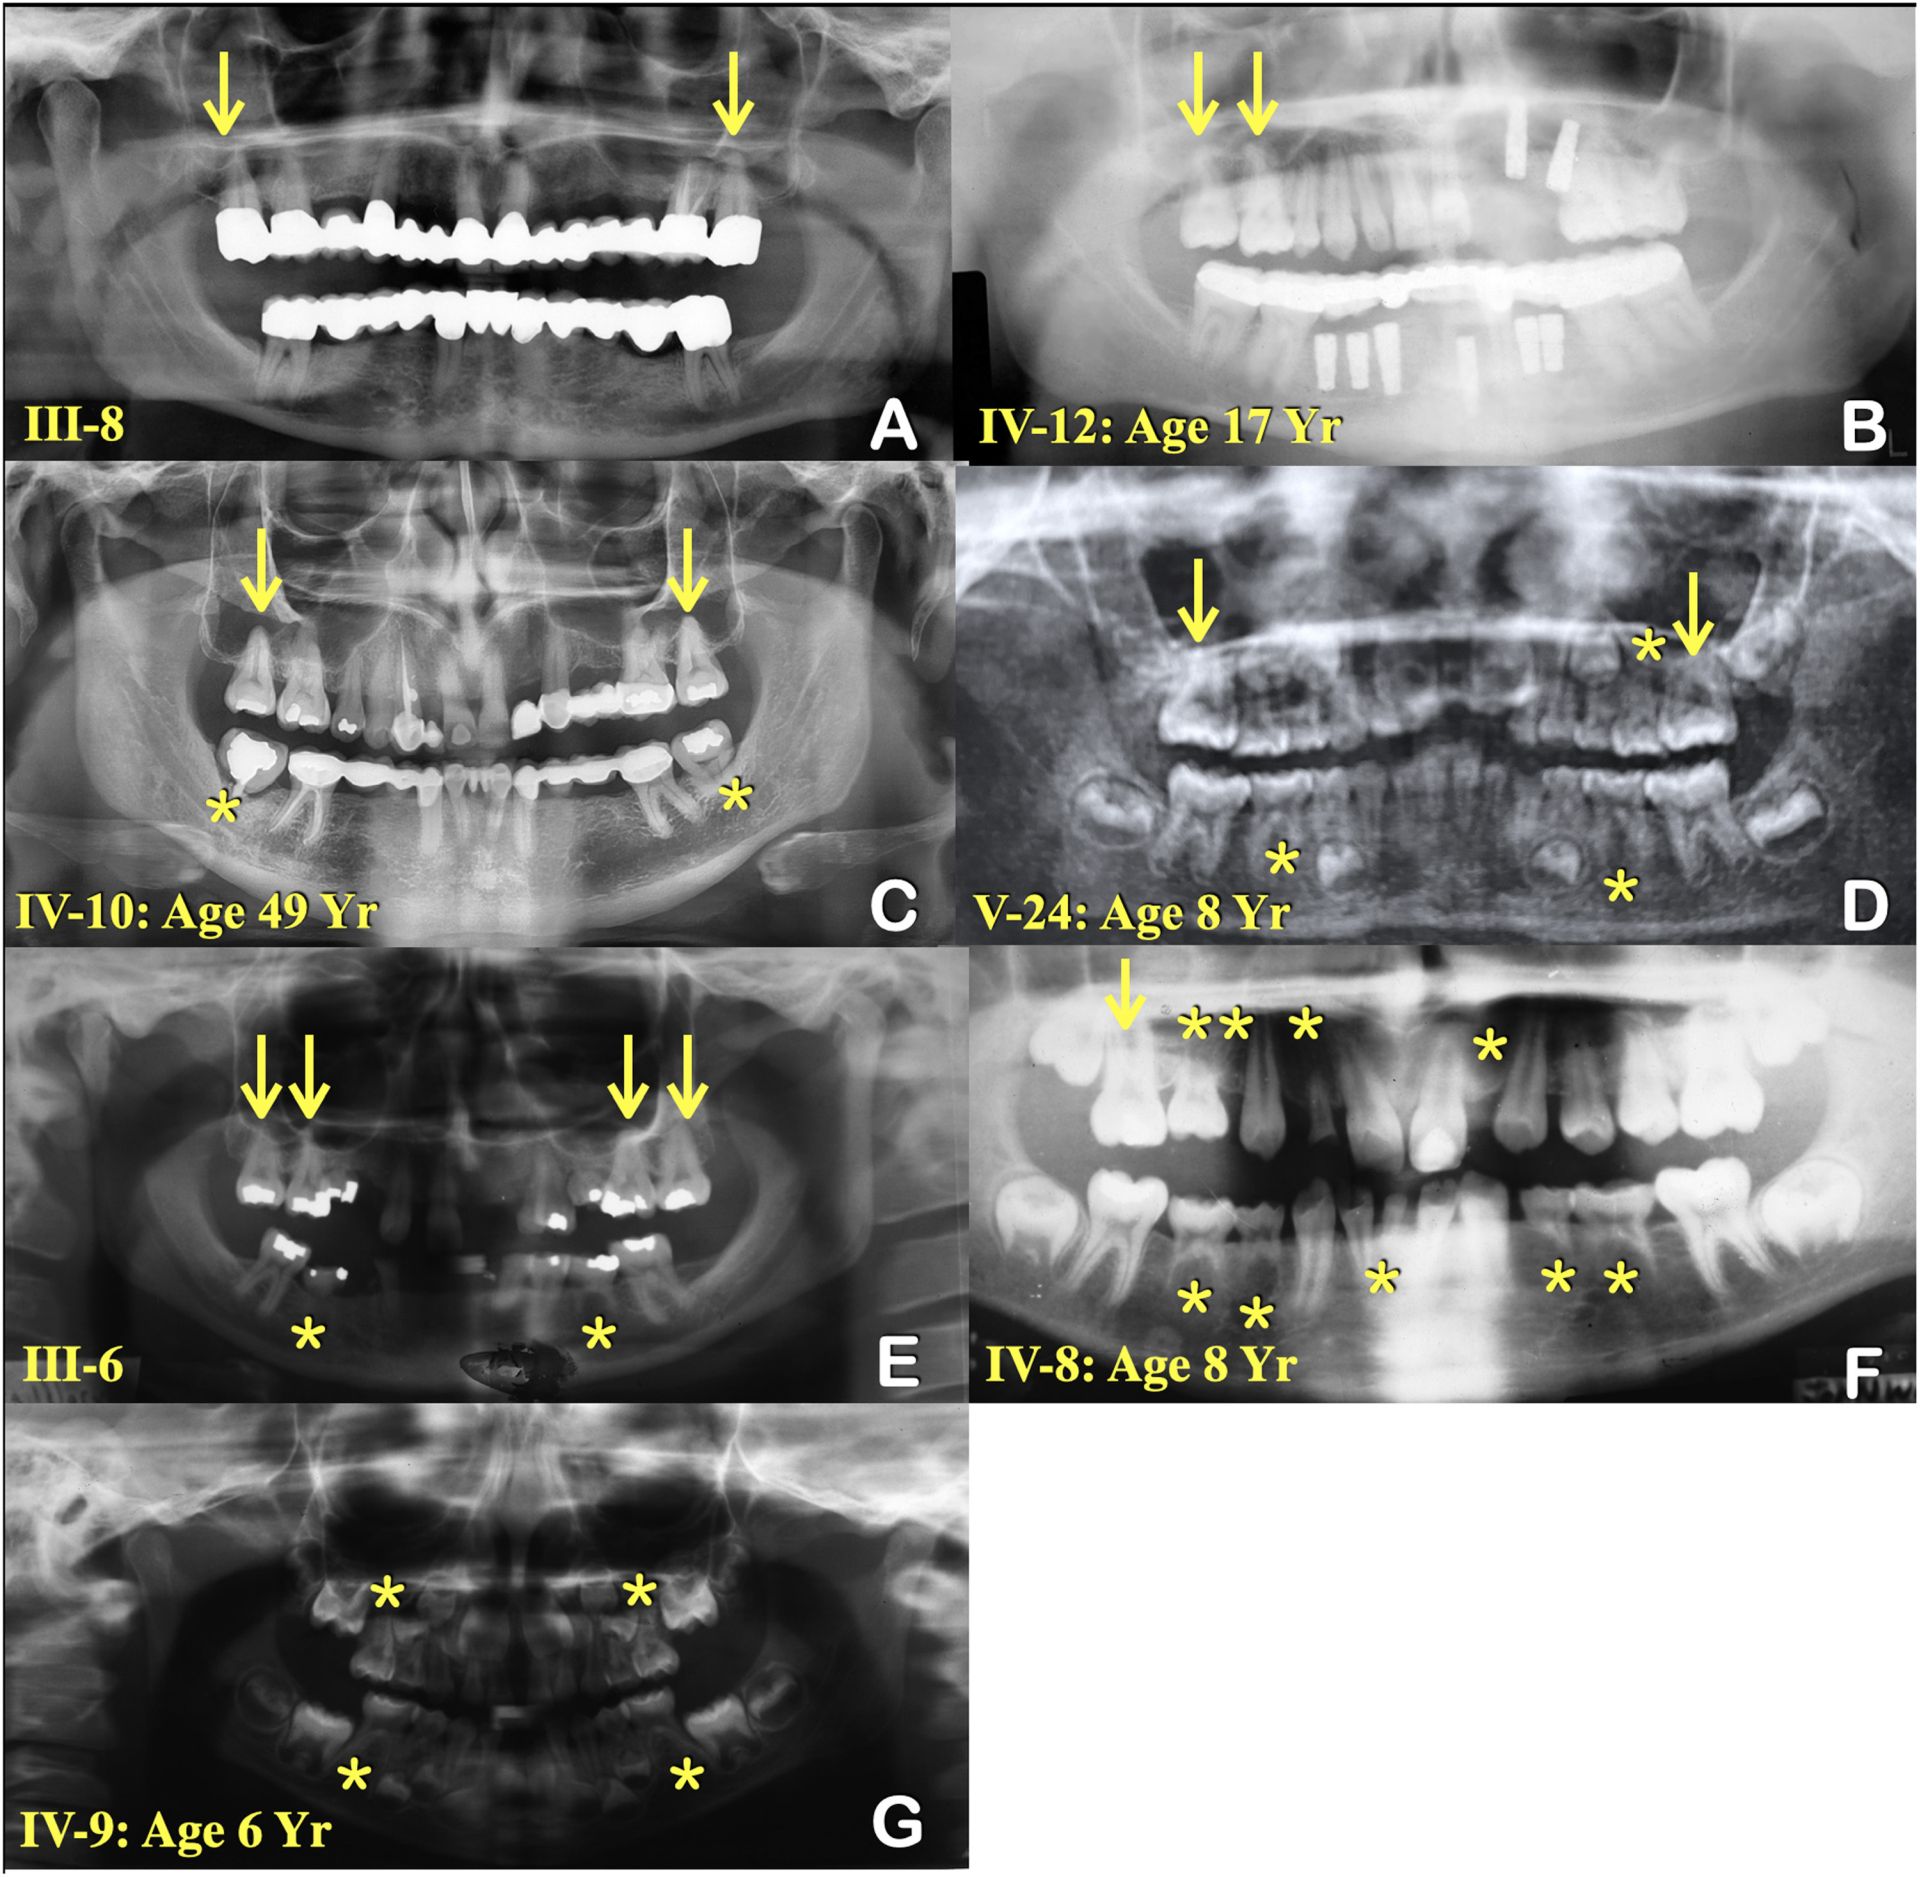

Graham s-a născut într-o familie în care lipsa dinților nu reprezenta o excepție, ci un adevărat mister. Deși la naștere a avut câțiva dinți, aceștia au căzut rapid, iar în locul lor nu au mai apărut dinți permanenți, ceea ce a dus la o formă severă de agenezie dentară. Anii au trecut, iar în ciuda tratamentelor și implanturilor necesare pentru restaurare, lipsa dinților a rămas o problemă ce i-a afectat încrederea în sine. Mai mult, această afecțiune a fost prezentă și la membrii familiei sale, atât la mama, cât și la frați, copiii și nepoți, ceea ce a sugerat o cauză genetică clară.

Cercetătorii au secvențiat genomul a patru membri ai familiei – doi afectați și doi sănătoși – și au comparat rezultatele pentru a identifica mutația responsabilă. În cele din urmă, analiza a condus spre o singură variantă genetica, situată pe o regiune specifică a cromozomului 1, unde se afla o mutație critică asupra genei KDF-1. Această genă codifică o proteină esențială pentru dezvoltarea pielii și a dinților, iar modificarea sa determină o structură instabilă a proteinei, ceea ce poate împiedica formarea corectă a dentiției la nivel genetic.

Verificările ulterioare pe un eșantion de 21 de membri ai familiei au susținut concluzia, varianta mutată fiind prezentă la 11 persoane afectate și absentă la cei sănătoși. Modelările computaționale au arătat că această mutație schimbă esențial o componentă a proteinei KDF-1, deformând-o și astfel perturbând rolul ei în procesul de dezvoltare dentară.